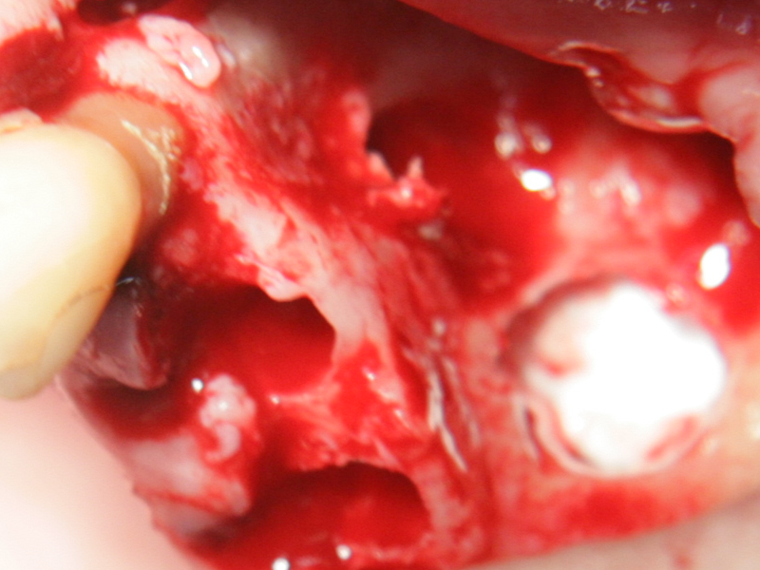

Отворен максиларен синус в началото на интервенцията. Случаят е интересен със следното - твърде атипична форма на трепанационния отвор. На какво се дължи на това - на лошо планиране на оперативния достъп или на нещо друго? Дължи се на факта, че отначало въпросната намеса беше планирана като балонен синуслифт; за съжаление обаче мембраната на синуса се разкъса и надуването на балона стана невъзможно.